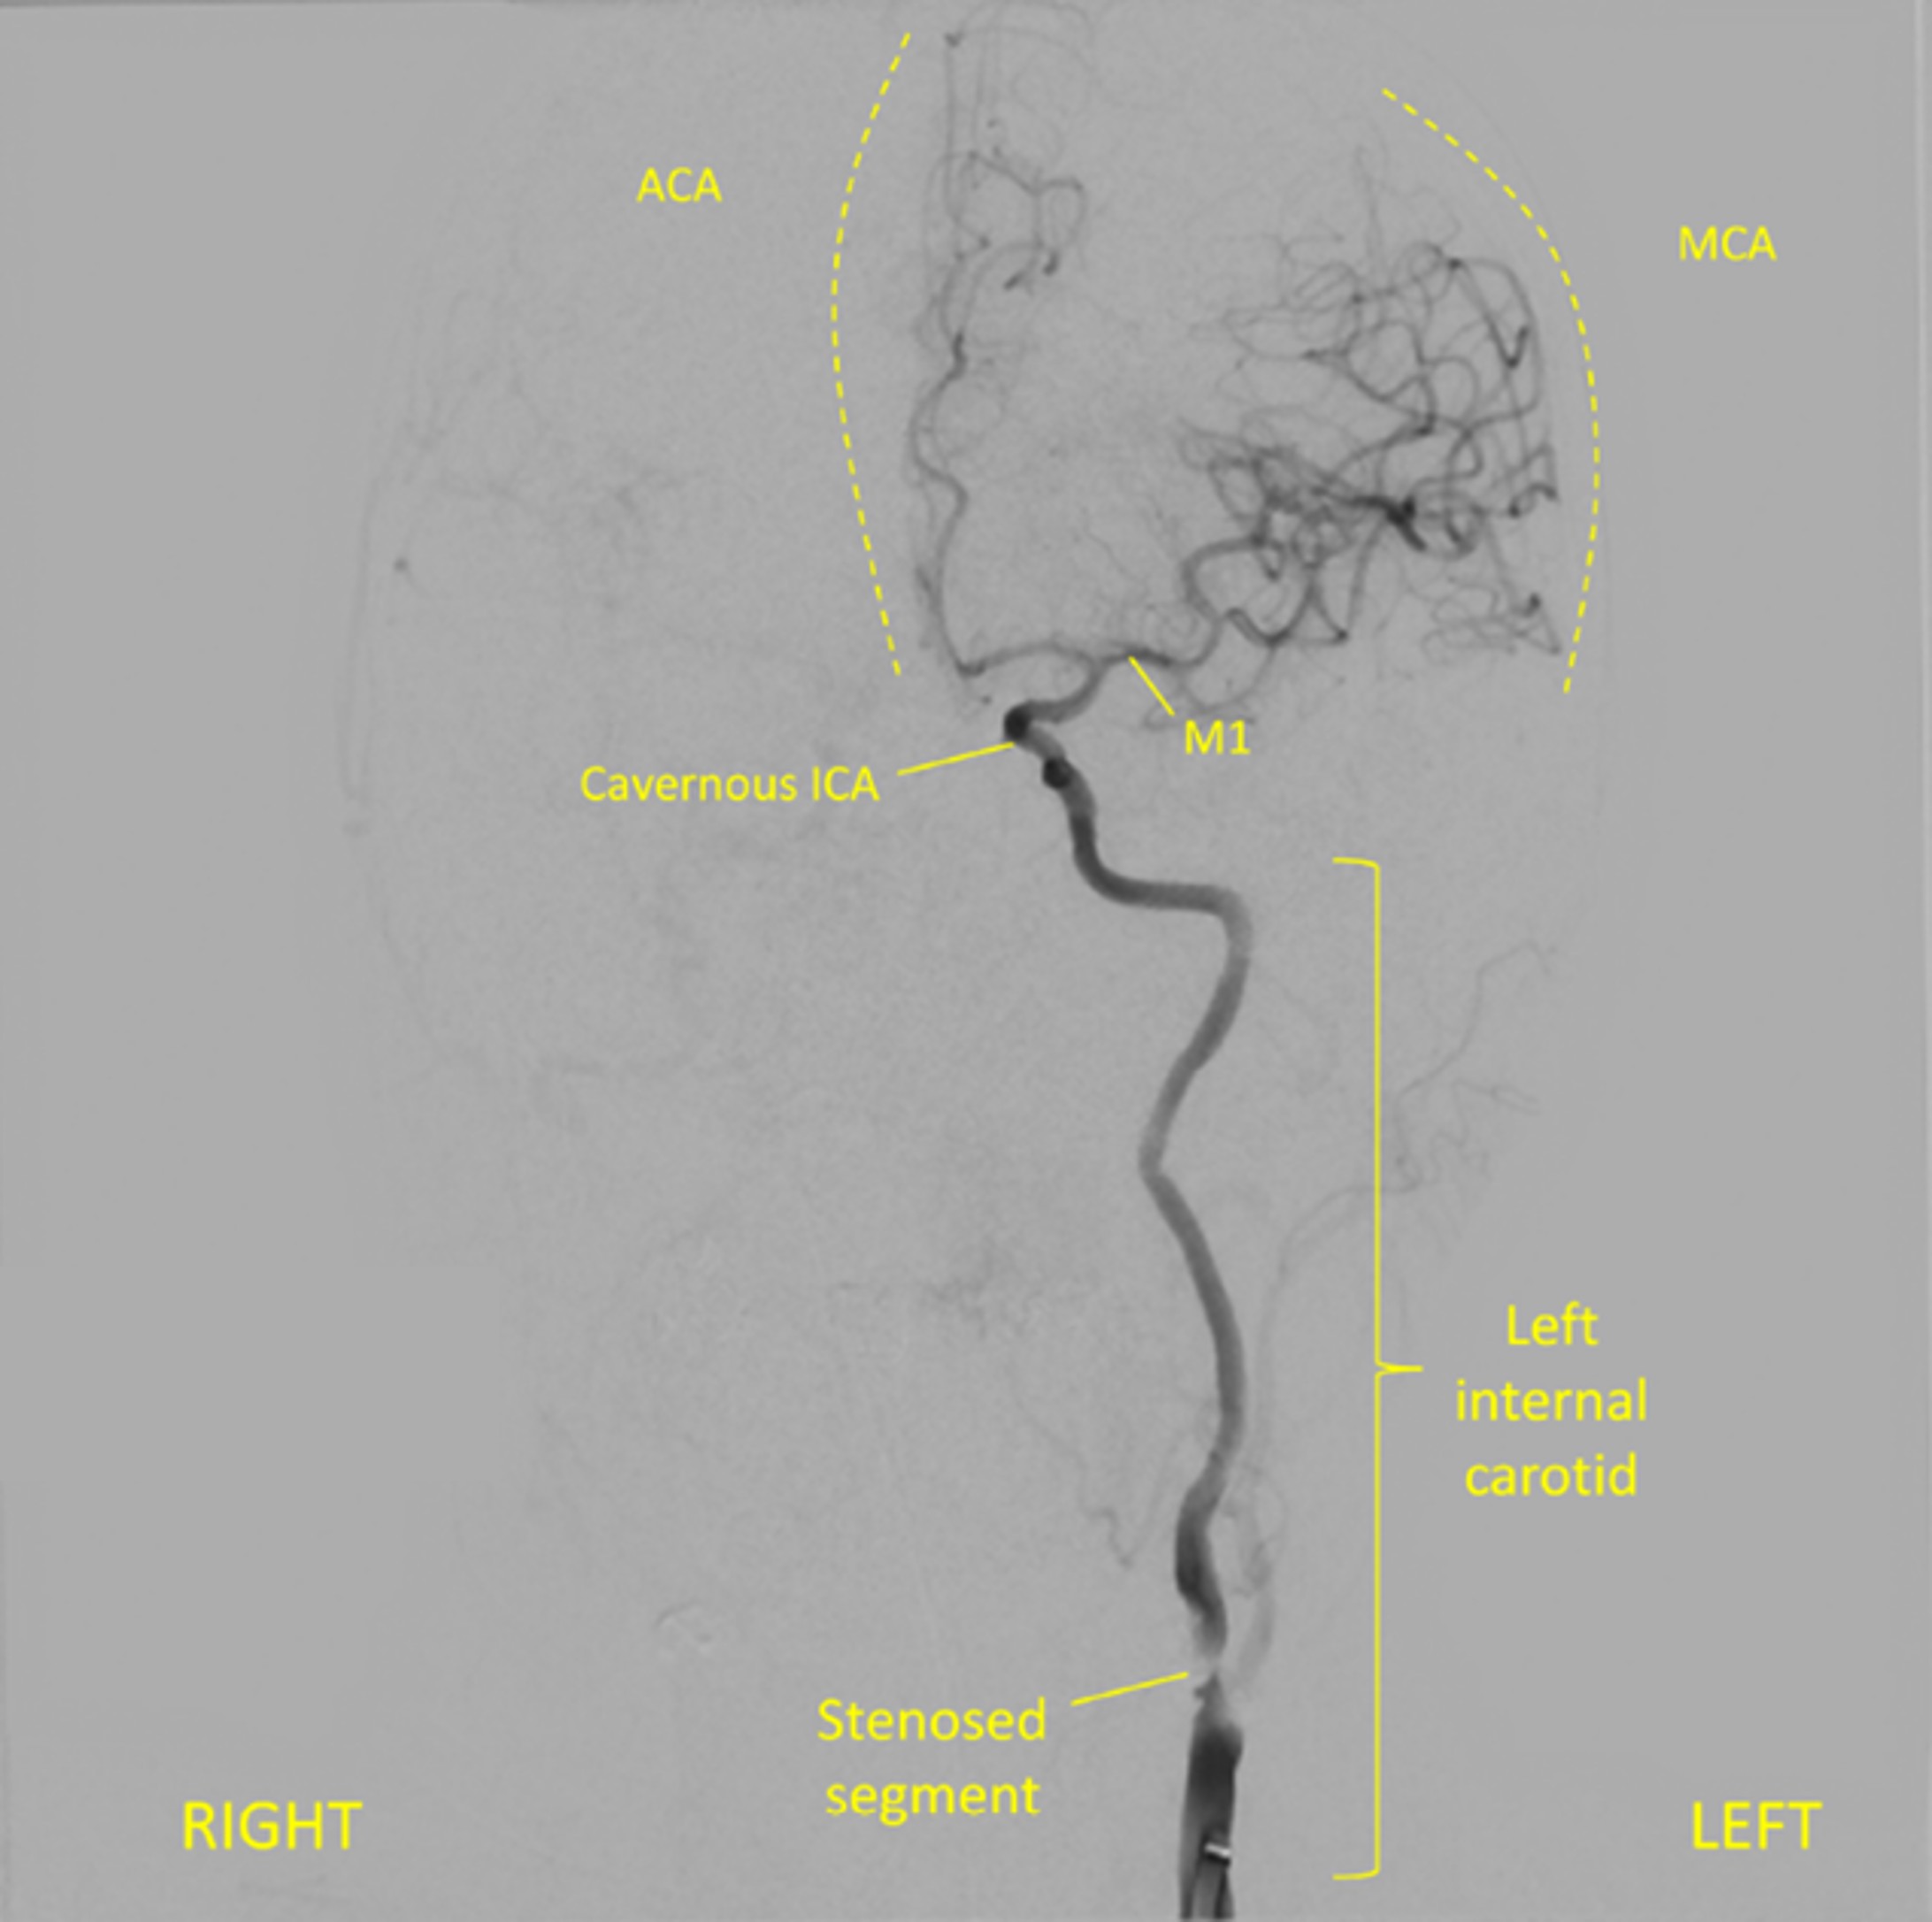

Her carotids were both significantly narrowed by atherosclerosis, particularly the left one - which was the likely source of the thrombus (artery-to-artery embolism).

The restored MCA circulation after the successful clot retrieval is shown on the coronal angiogram below.

Angiography